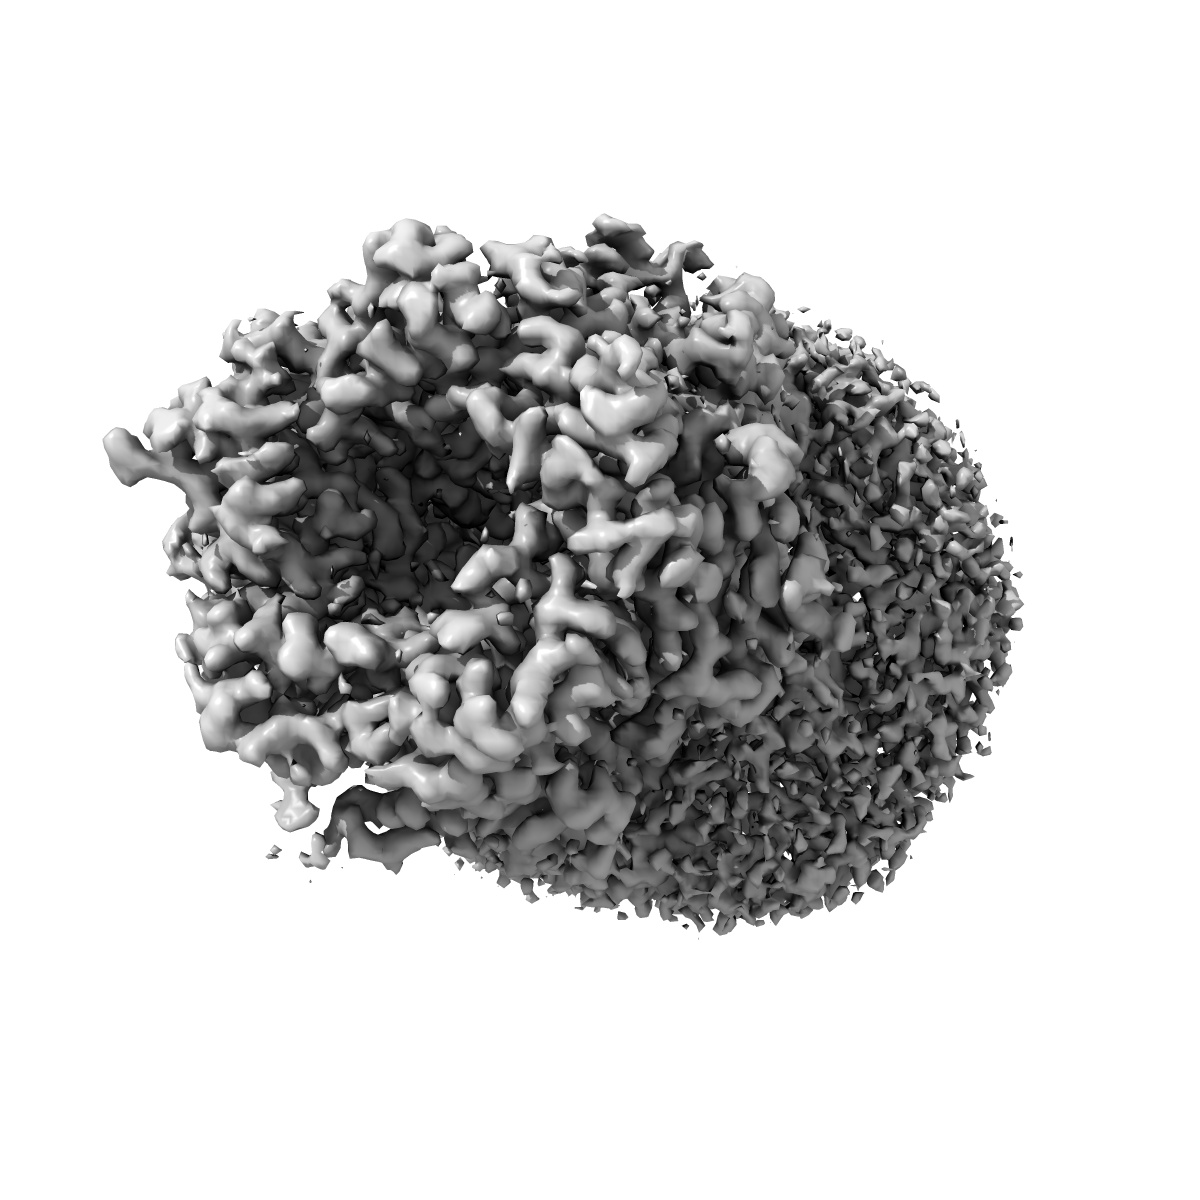

Cryo-EM structure of Torpedo acetylcholine receptor in complex with d-tubocurarine

EMD-25207

Single-particle

3.18 Å

Sample Organism: Tetronarce californica

Sample: Torpedo acetylcholine receptor in complex with d-tubocurarine

Fitted models: 7sms

Deposition Authors: Rahman MM , Basta T

Structural mechanism of muscle nicotinic receptor desensitization and block by curare.

Rahman MM , Basta T, Teng J, Lee M, Worrell BT, Stowell MHB , Hibbs RE

(2022) Nat Struct Mol Biol , 29 , 386 - 394